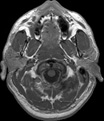

Visible Human male: Sectio transversalis 1164

NMR

Pd T1 T2